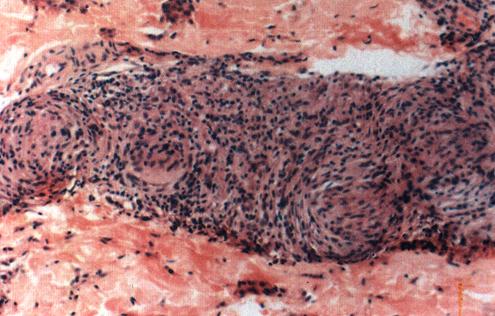

照片5 界线类偏瘤型麻风(BL)

巨噬细胞浸润灶,淋巴细胞多,分散存在,可见神经束膜呈明显葱皮样变。